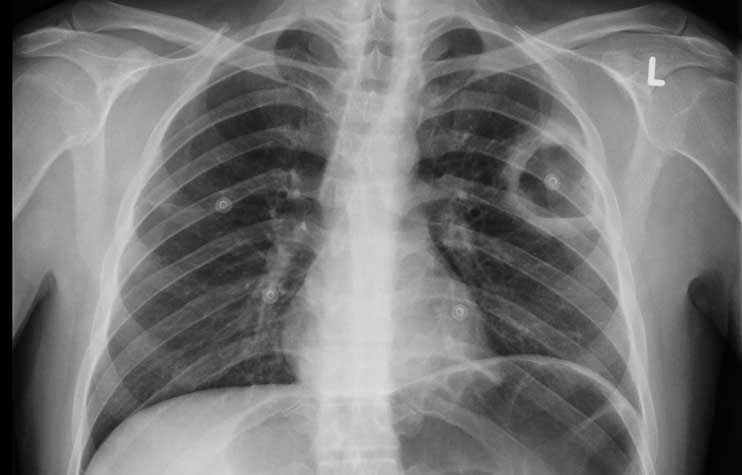

Röntgen-Thorax

Der konvetionelle Röntgen-Thorax hat sich im Laufe der Zeit zu einem unverzichtbaren zentralen Bestandteil in der Diagnostik sowie zur Beurteilung des Therapieverlaufes zahlreicher Herz- und Lungenerkrankungen entwickelt. Des Weiteren spielt er eine wichtige Rolle in der Beurteilung der Narkose- und Untersuchungsfähigkeit eines Patienten. Nicht selten liefert er relevante Nebendiagnosen der Lunge oder des Skelettes (Tumoren, asbestinduzierte Lungenveränderungen, Wirbelkörper- oder Rippenbrüche, Schilddrüsenerkrankungen etc.).

Darstellung von Erkrankungen im Röntgen-Thorax:

Die Vorteile des Röntgen-Thorax liegen in der schnellen Verfügbarkeit zu allen Tages-, und Nachtzeiten ohne spezielle Vorbereitung des Patienten. So können Erkrankung wie beispielsweise eine Lungenentzündung oder eine kardiopulmonale Kreislaufentgleisung gut erkannt und rechtzeitig therapiert werden. Aber auch akut lebensbedrohliche Erkrankungen wie der Spannungspneumothorax können sicher ausgeschlossen werden.

Selbst bei bettlägerigen Patienten ist ein Röntgen-Thorax im Liegen mit guter Aussagekraft durchführbar.

Die Lage von eingebrachten Fremdkörpern (zentralen Kathetern, Herzschrittmacher sowie Defibrillator, Magensonde, Herzklappen, Trachealtubus etc.) kann, wie auch versehentlich verschluckte oder durch Unfall inkorporierte Fremdkörper grundsätzlich gut beurteilt werden.

Darüber hinaus hat der Röntgen-Thorax den Vorteil einer sehr niedrigen Strahlendosis (im Schnitt um den Faktor 300 niedriger als im vergleichbaren Thorax- CT).

Selten und erst bei schwierigen Bildkonstellationen oder fehlender Übereinstimmung mit den Beschwerden des Patienten ist eine weiterführende Abklärung mittels aussagekräftigerer aber strahlungsintensiverer Computertomographie (CT) nötig.